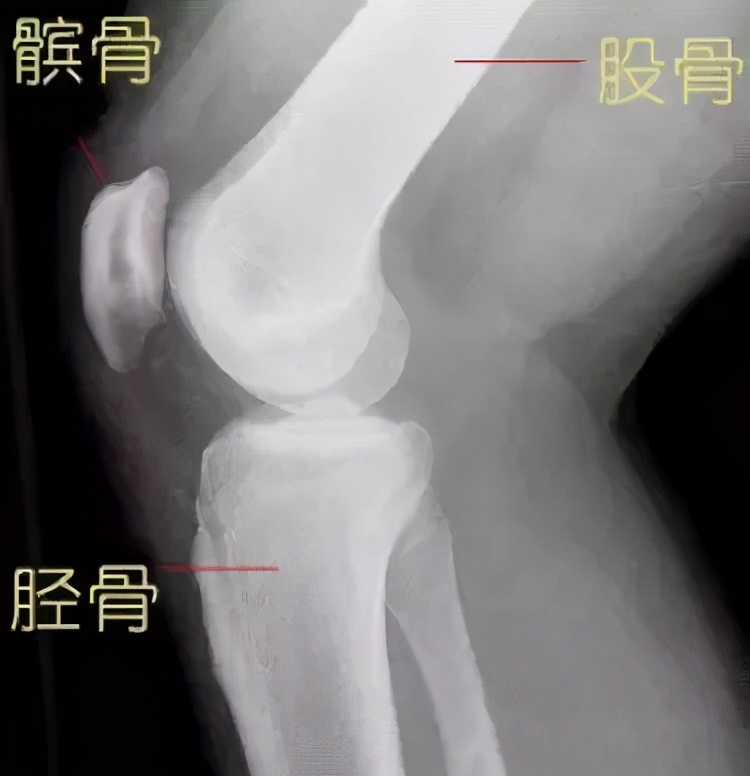

膝关节作为人体最大最复杂的关节,由股骨下端、胫骨上端和髌骨共同构成。其中胫骨上端基本上是一个平面,而股骨下端的关节面则是一个椭圆形,两个关节面一圆一平,并不完全贴和,所以需要半月板来帮助关节面完整贴和[2]。

膝关节X光片(矢状面)